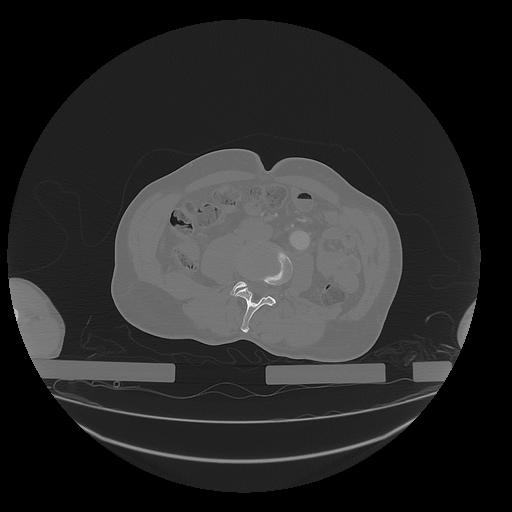

31 PULMON,CE,Vol,1.0,PULMON,,